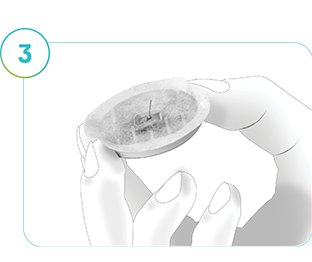

Steg 3

Inspektera baksidan av den borttagna sensorn för att säkerställa att den stiftliknande delen sitter kvar. Det är viktigt att bekräfta att den har avlägsnats från din hud. Titta/känn på huden runt applikationsstället för att kontrollera.

Kontakta din läkare/diabetessköterska omedelbart om:

- Stiftet inte är borttaget från resten av sensorn eller sitter kvar i huden.

- Du får smärta, svullnad, rodnad eller andra ovanliga symtom.

- Du får känningar i eller i närheten av applikationsstället.